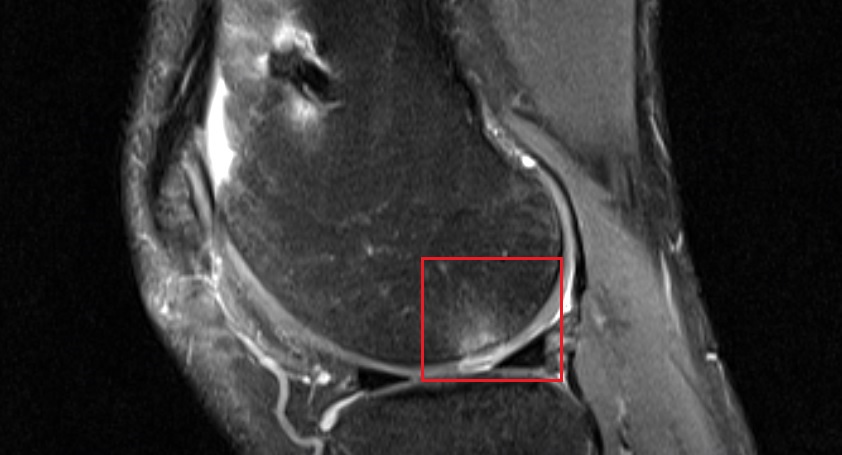

Hier siehst du noch ein MRT Bild, 2 Tage nach dem Trauma. Ich habe mal kenntlich gemacht, wo das Stück herausgebrochen ist und wie groß es ist. Man sieht hier gut, dass es lateral hinter der Partella herausgebrochen ist und im Gelenk "herumlag". Man kann auch gut erkennen, weshalb es bei der Überstreckung an dieser Stelle herausgebrochen ist.